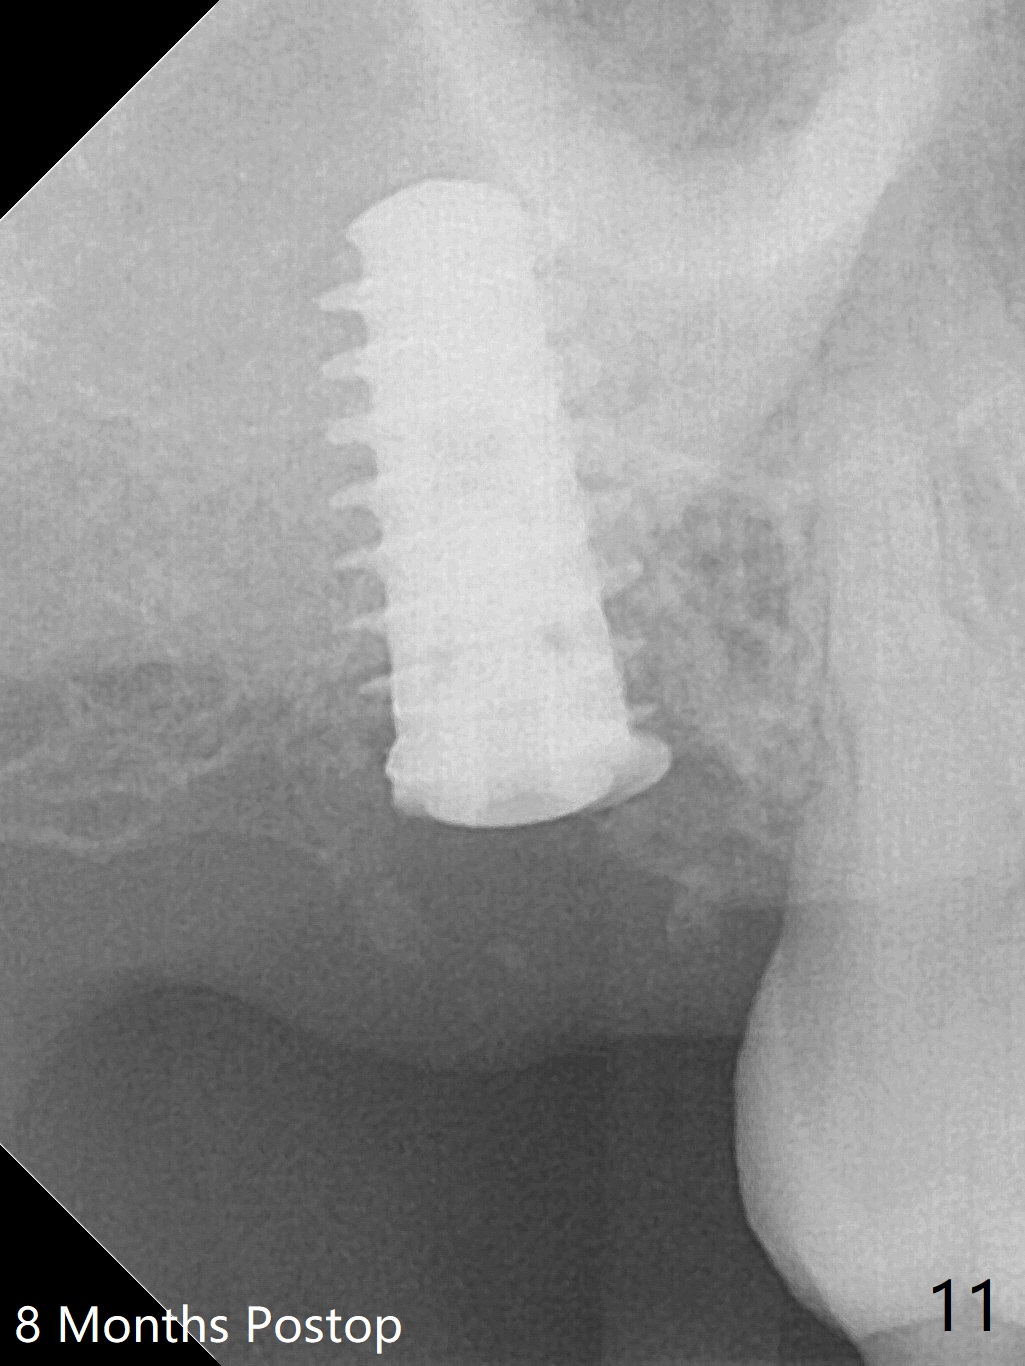

The implant is stable with the healing abutment 8 months postop (Fig.11). There is definitive sign of osteointegration 12 months postop (3 months post cementation, Fig.12). The patient is pleased to have the implant for 1 year 7.5 months post cementation (Fig.13).